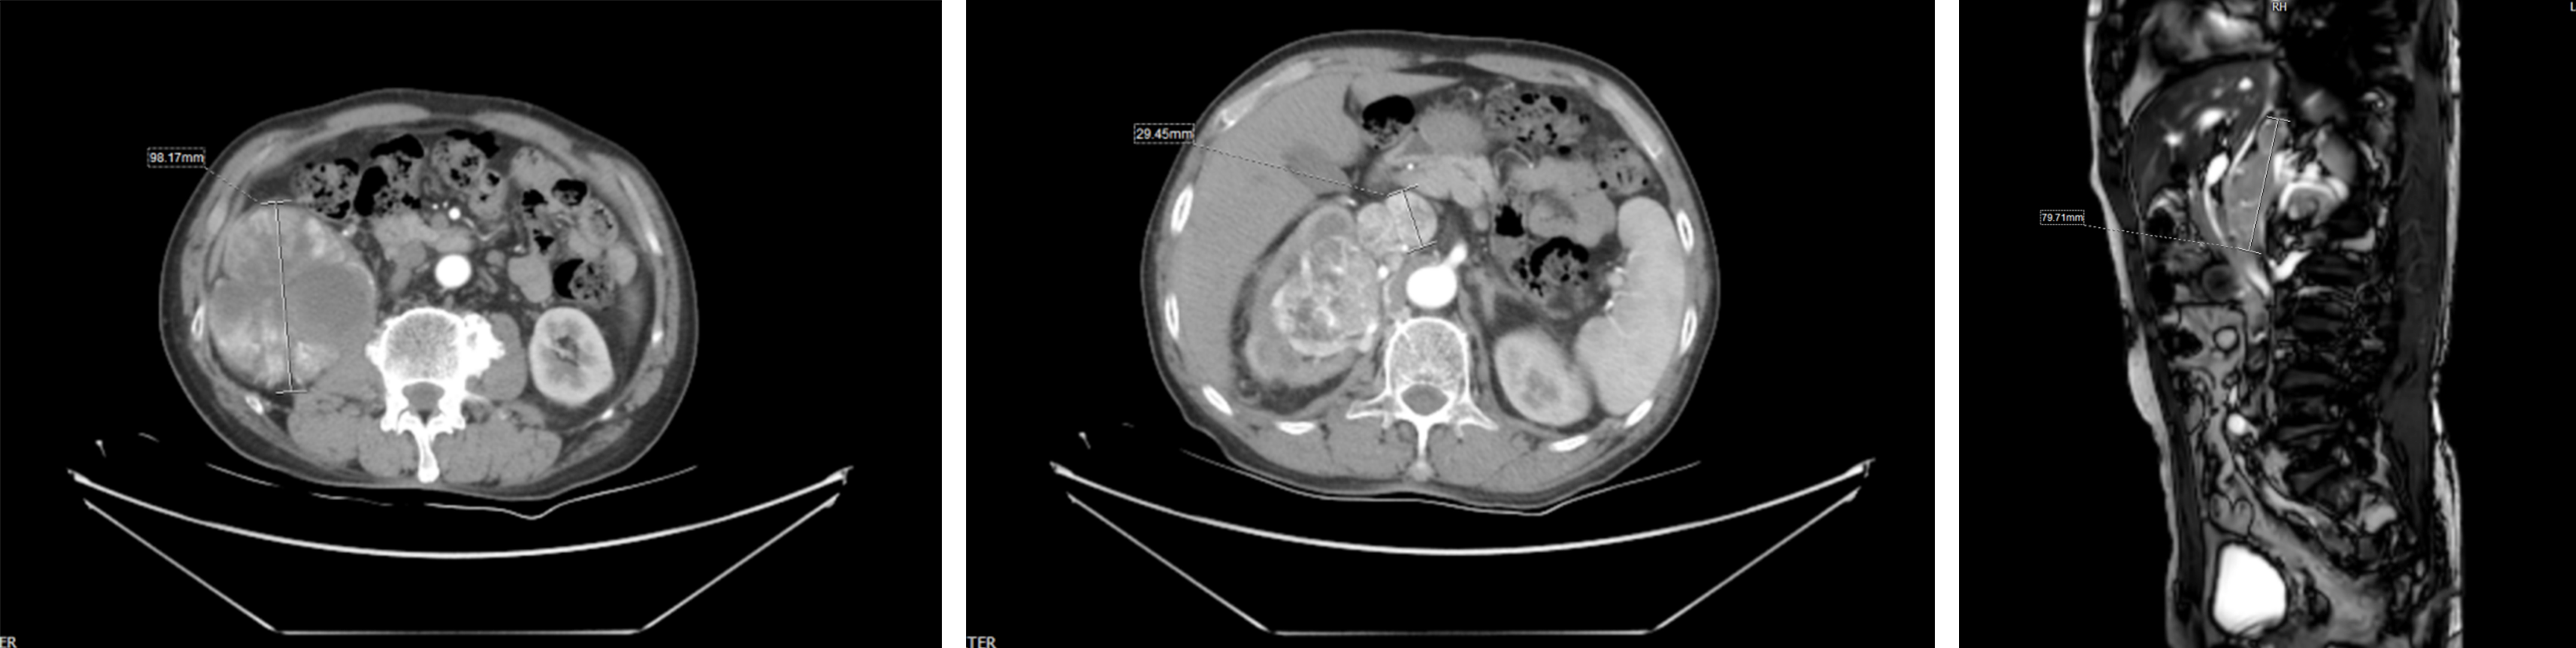

患者为76岁男性,因双下肢水肿半年余入院治疗。入院后完善相关检查,明确诊断为右肾恶性肿瘤、右肾上腺继发转移瘤、腔静脉癌栓、右肾蒂多发淋巴结转移,临床分期为T4N1M0,腔静脉癌栓III级(Mayo分级)。经MDT讨论并综合评估后,拟行手术治疗,尚攀峰教授团队首先在达芬奇机器人辅助腹腔镜下充分游离出肾脏及巨大瘤体,暴露出下腔静脉,为确保手术万无一失,决定中转开放手术,普通外科杨含腾主任医师协助翻肝,游离出肝脏平面下腔静脉段,完整显露出癌栓的上界。随后阻断下腔静脉近远端及其分支,剖开下腔静脉,切除癌栓及粘附的部分血管壁,严密缝合下腔静脉切口,开放血流后无明显渗血。同时,完整切除右侧肾脏肿瘤、淋巴结、肾上腺转移瘤,取出下腔静脉癌栓。经术后精心治疗,患者1周后康复出院。